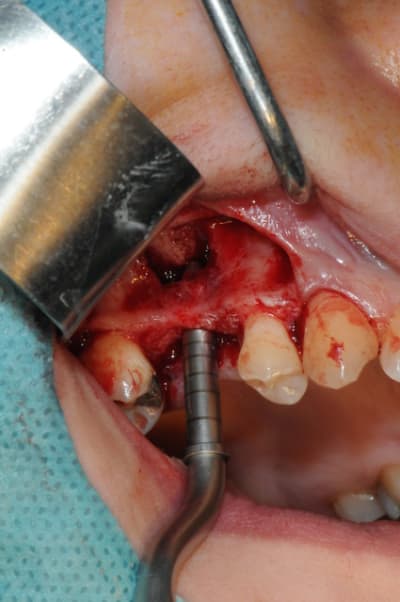

je sais pas si c'est un produit miracle, mais pour les sinus lift, c'est fantastique.

outre le fait de stabiliser un implant dans un sinus type SA4, pas de risque de voir partir le produit comme avec les granules de bioos et autres..

l'autre avantage est de ne pas avoir à mettre de membrane de recouvrement.

je suis donc hyper satisfait du résultat.

jugez plutôt...

l'application type du VitalOs, avec le bone splitting.

Chapeau gamin c'est très propre et très bien iconographié.

le protocole tel qu'il est d'écrit voudrait que l'on applique d'abord une couche de vital os en palatin - laisser durcir - mettre l'implant puis mettre une dernière couche.

ici, j'ai mis l'implant- maintenu la membrane de Schneider en poussant avec l'embout sur celle ci et terminer l'injection du produit. c'est l'un des avantages de ce produit, il est livré avec deux embouts donc les deux solutions sont possibles pour une même seringue.